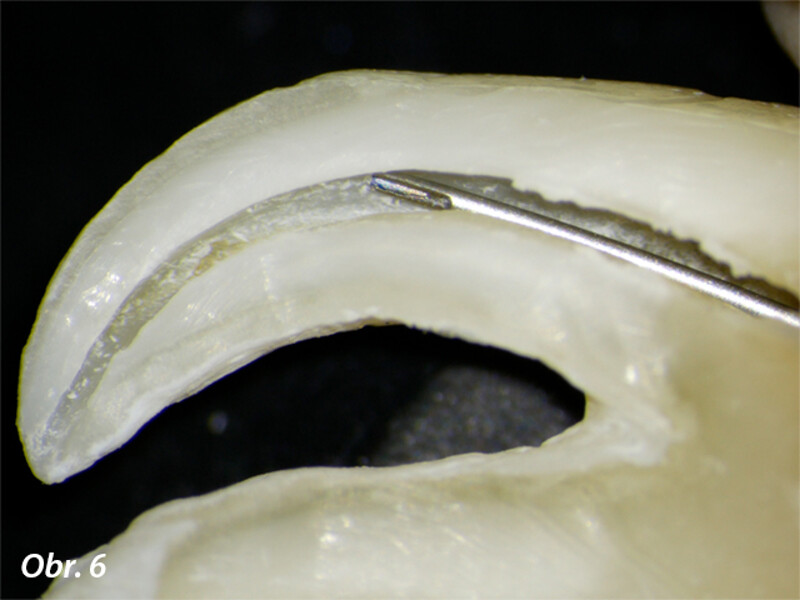

Vyplachování zahnutých kanálků